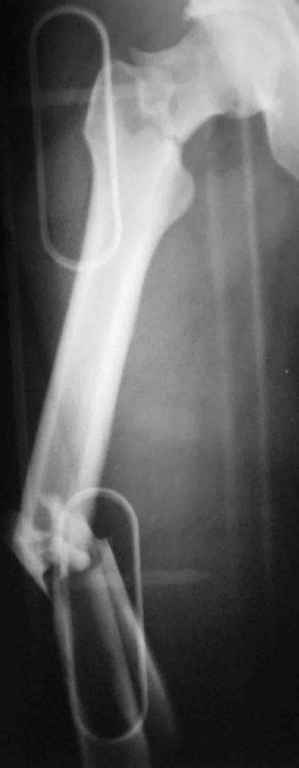

Уважаемый Сергей, избрав вариант DHS плюс ретроградный гвоздь Вы явно обезопасите себя от проблем, связанных с введением штифта через trochanteric fossa. Очень это может быть проблематично, Вы правы. Поэтому DHS плюс ретроградный гвоздь - спокойно выполнимый вариант, особенно в "чужом" отделении. Схожий свой случай из далёкого теперь уже 1999г. прилагаю, только вместо канюлированных винтов у Вас будет DHS (VHS). А если антеградный гвоздь - то только из тех, что предназначены к введению через верхушку вертела. И это тоже выполнимо, но сложнее. Мне так кажется.